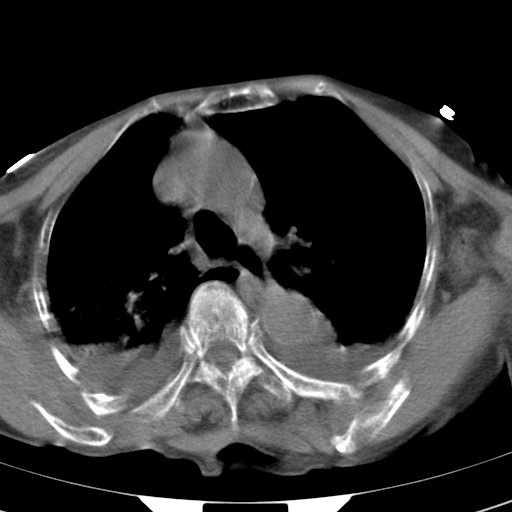

标题: CT21467:女,93岁,摔伤后检查。 [打印本页]

女,93岁,摔伤后检查。

右肺炎症,心功能不全伴双侧胸腔积液,右下肺膨胀不全,食管裂孔疝,冠脉钙化,心包少量积液,左侧肋骨骨折,请上传骨窗.

右侧锁骨\\肩胛骨骨折、右侧湿肺,心功能不全伴双侧胸腔积液,右下肺膨胀不全,左膈破裂或食管裂孔疝,冠脉钙化,心包少量积液,请上传骨窗.

右肺炎症,心功能不全伴双侧胸腔积液,右下肺膨胀不全,食管裂孔疝,冠脉钙化,心包少量积液,左侧肋骨骨折,右肩甲骨粉碎性骨折。93岁,高寿哇!